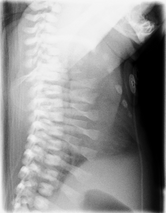

Lateral CXR of the same person above

Jeune syndrome is a rare autosomal recessive ciliopathy.[8]

This diagnosis is grouped with other chest problems called thoracic insufficiency syndrome (TIS). Diagnosis of Jeune syndrome can be made as early as before birth if signs and symptoms are apparent on an ultrasound; however, diagnosis after birth usually occurs through X-rays and genetic testing, such as the tests found on the Genetic Testing Registry Archived 2021-03-18 at the Wayback Machine (GTR).[9]